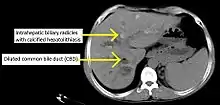

Historically, a cholangiogram would be obtained via endoscopic retrograde cholangiopancreatography (ERCP), which typically reveals "beading" (alternating strictures and dilation) of the bile ducts inside and/or outside the liver. Currently, the preferred option for diagnostic cholangiography, given its noninvasive yet highly accurate nature, is magnetic resonance cholangiopancreatography (MRCP), a magnetic resonance imaging technique. MRCP has unique strengths, including high spatial resolution, and can even be used to visualize the biliary tract of small animal models of PSC.[19]